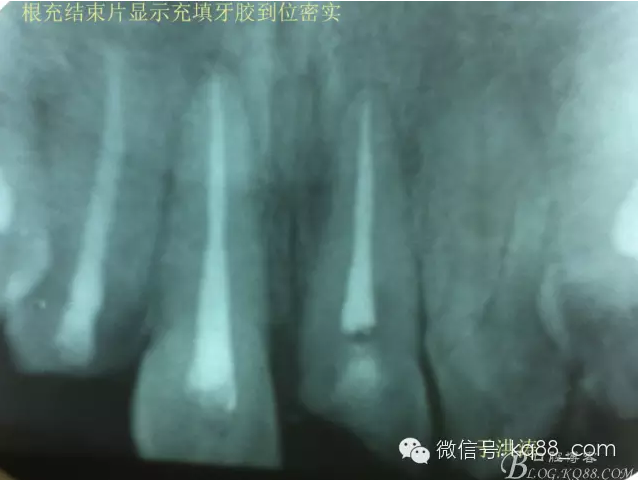

治療過程:經(jīng)患者同意。H銼去除11 21原有充填物,未發(fā)現(xiàn)明顯滲出物,無異味。K銼疏通根管,VDW根測儀測量長度,11牙20mmWL,21牙20mmWL。S3鎳鈦器械預(yù)備根管。(全程1%次氯酸鈉沖洗EDTA溶解潤滑)試尖片顯示牙膠未到位,繼續(xù)向牙根尖各2mm進入預(yù)備。吸潮紙尖吸干根管,登士柏樹脂根充糊劑輸送至根尖部位,以測量數(shù)據(jù)用牙膠尖冷充側(cè)壓充填根管,3M玻璃離子封閉根管口。不可用患牙啃咬硬物,擇日冠修復(fù)。

輔助檢查:插針X線片顯示根管內(nèi)充填物已經(jīng)取出。試尖片顯示牙膠尖未到位,繼續(xù)用K銼和機括向根尖預(yù)備。根充結(jié)束片顯示根充密實,無超充,無欠充。